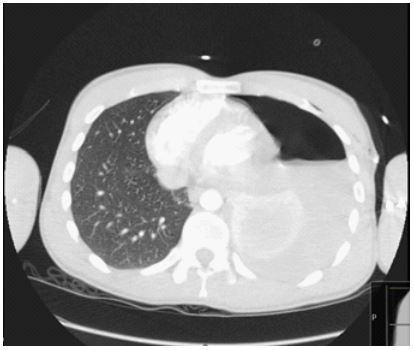

On the guidance of the cardiothoracic specialists, a chest tube was placed, which drained 950 ml of fresh blood using the Seldinger procedure, and then clamped. We administered IV fluids and PRBCs were given. It was decided to perform a chest CT scan with contrast (Figure 2). Following a surgical examination, the chest tube was unclamped, which immediately caused a 700 ml of blood loss. Vital signs of the patient remained stable.

Figure 2: CT scan of the chest revealing the left sided airfluid level of the haemopneumothorax with the collapsed left lung